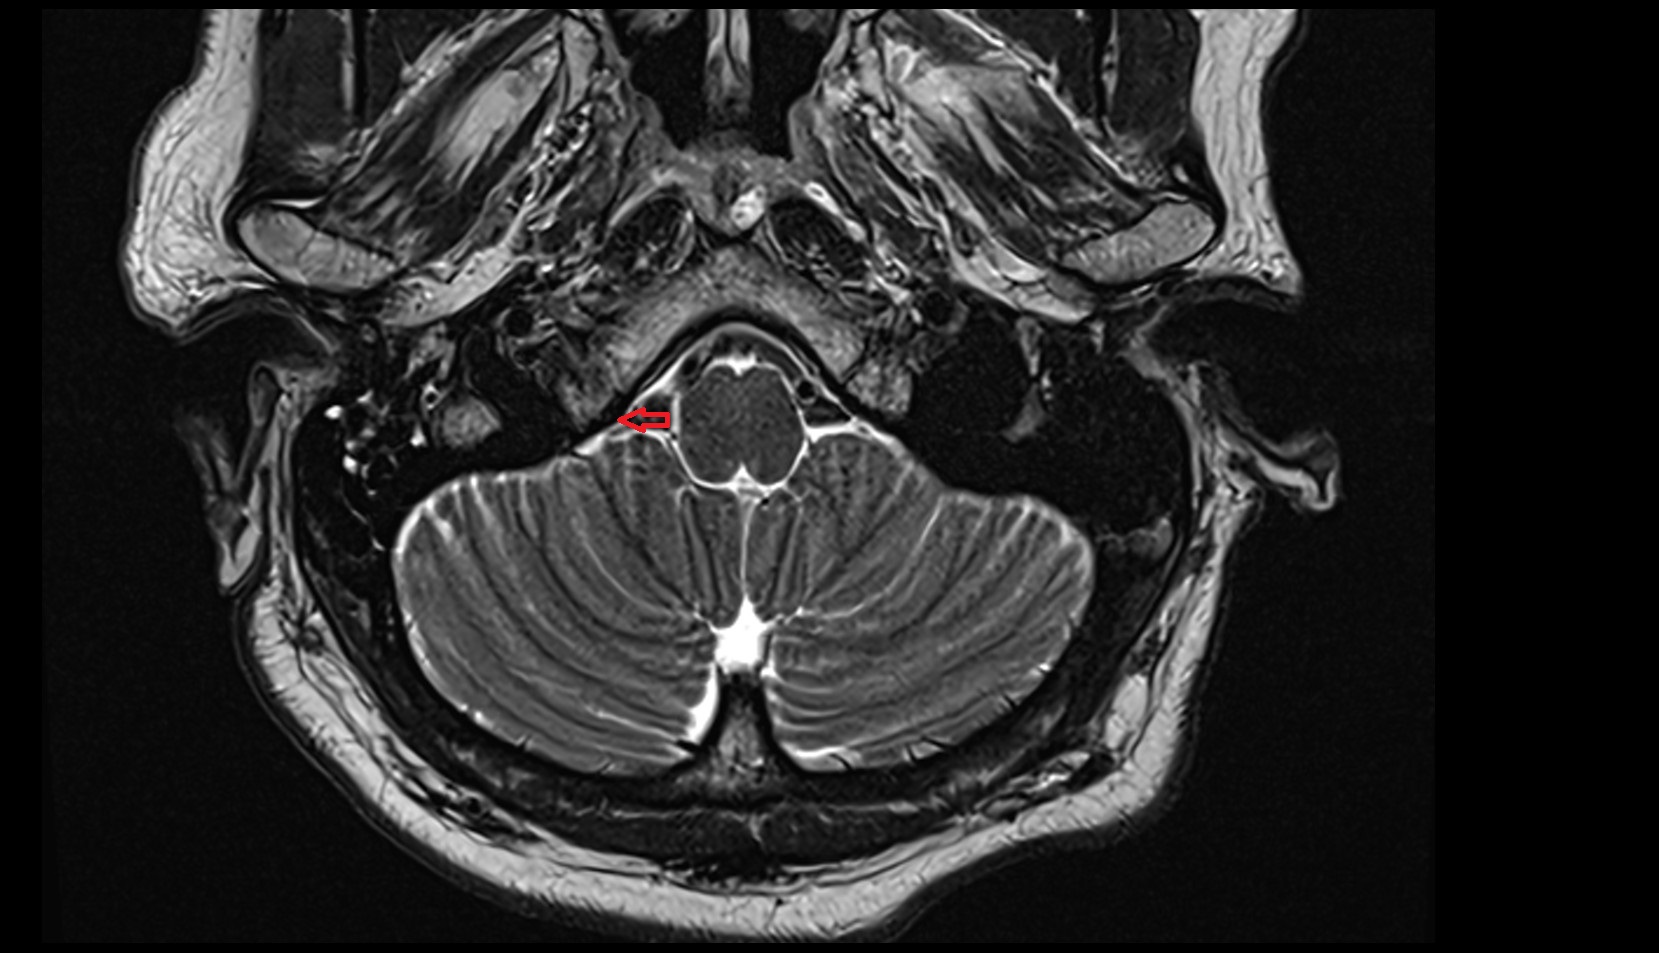

- Lateral aperture of fourth ventricle (foramen of Luschka)

- Flocculus